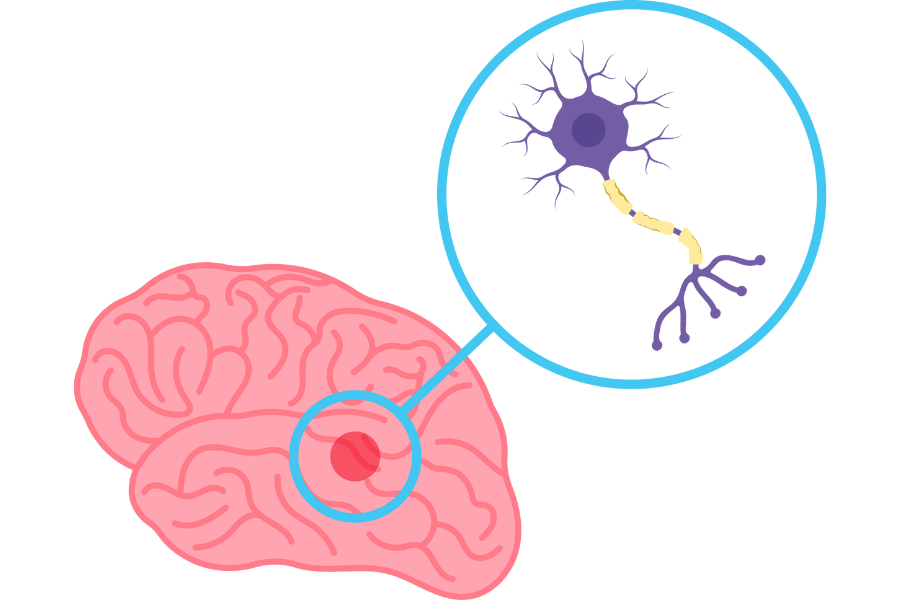

Nastane zaradi degeneracije nevronov, ki proizvajajo dopamin v bazalnih ganglijih. Dopamin je živčni

prenašalec, ki je bistven za nadzor gibanja in koordinacije. Ko se raven dopamina zmanjša, pride do

motenj pri prenosu signalov v možganih, kar povzroča značilne simptome bolezni, kot so tresenje,

Za boljšo oceno lahko zdravnik uporablja dodatne diagnostične preiskave, npr. slikanje možganov, pri čemer se pogosto uporabi DaTscan, posebno vrsto slikanja, ki omogoča oceno aktivnosti dopamina v

bazalnih ganglijih možganov. DaTscan uporablja posebno radioaktivno snov, ki se veže na

dopaminske receptorje, kar omogoča zdravniku, da oceni morebitne spremembe v strukturi in

funkciji možganov, ki so značilne za Parkinsonovo bolezen.